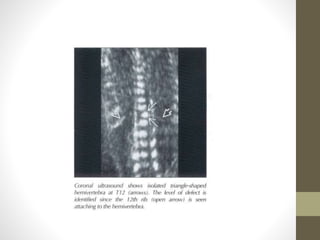

SPINE

WHAT TO SEE? IN SPINE

โ€ข 1. CRANIVERTERBERAL JUNCTION ABNORMALITIES

โ€ข 2. ALIGMENT

โ€ข KYPHOSIS/SCOLIOSIS

โ€ข 3. THREE OSSEOUS ELEMENTS

โ€ข SKIN CONTUNITY

โ€ข ABSENT OR FLARING OF POSTERIOR ELEMENTS

โ€ข 4.SACRUM

โ€ข CAUDAL REGRESSION SYNDROME

โ€ข 5. NUMBER

Curvature Abnormality